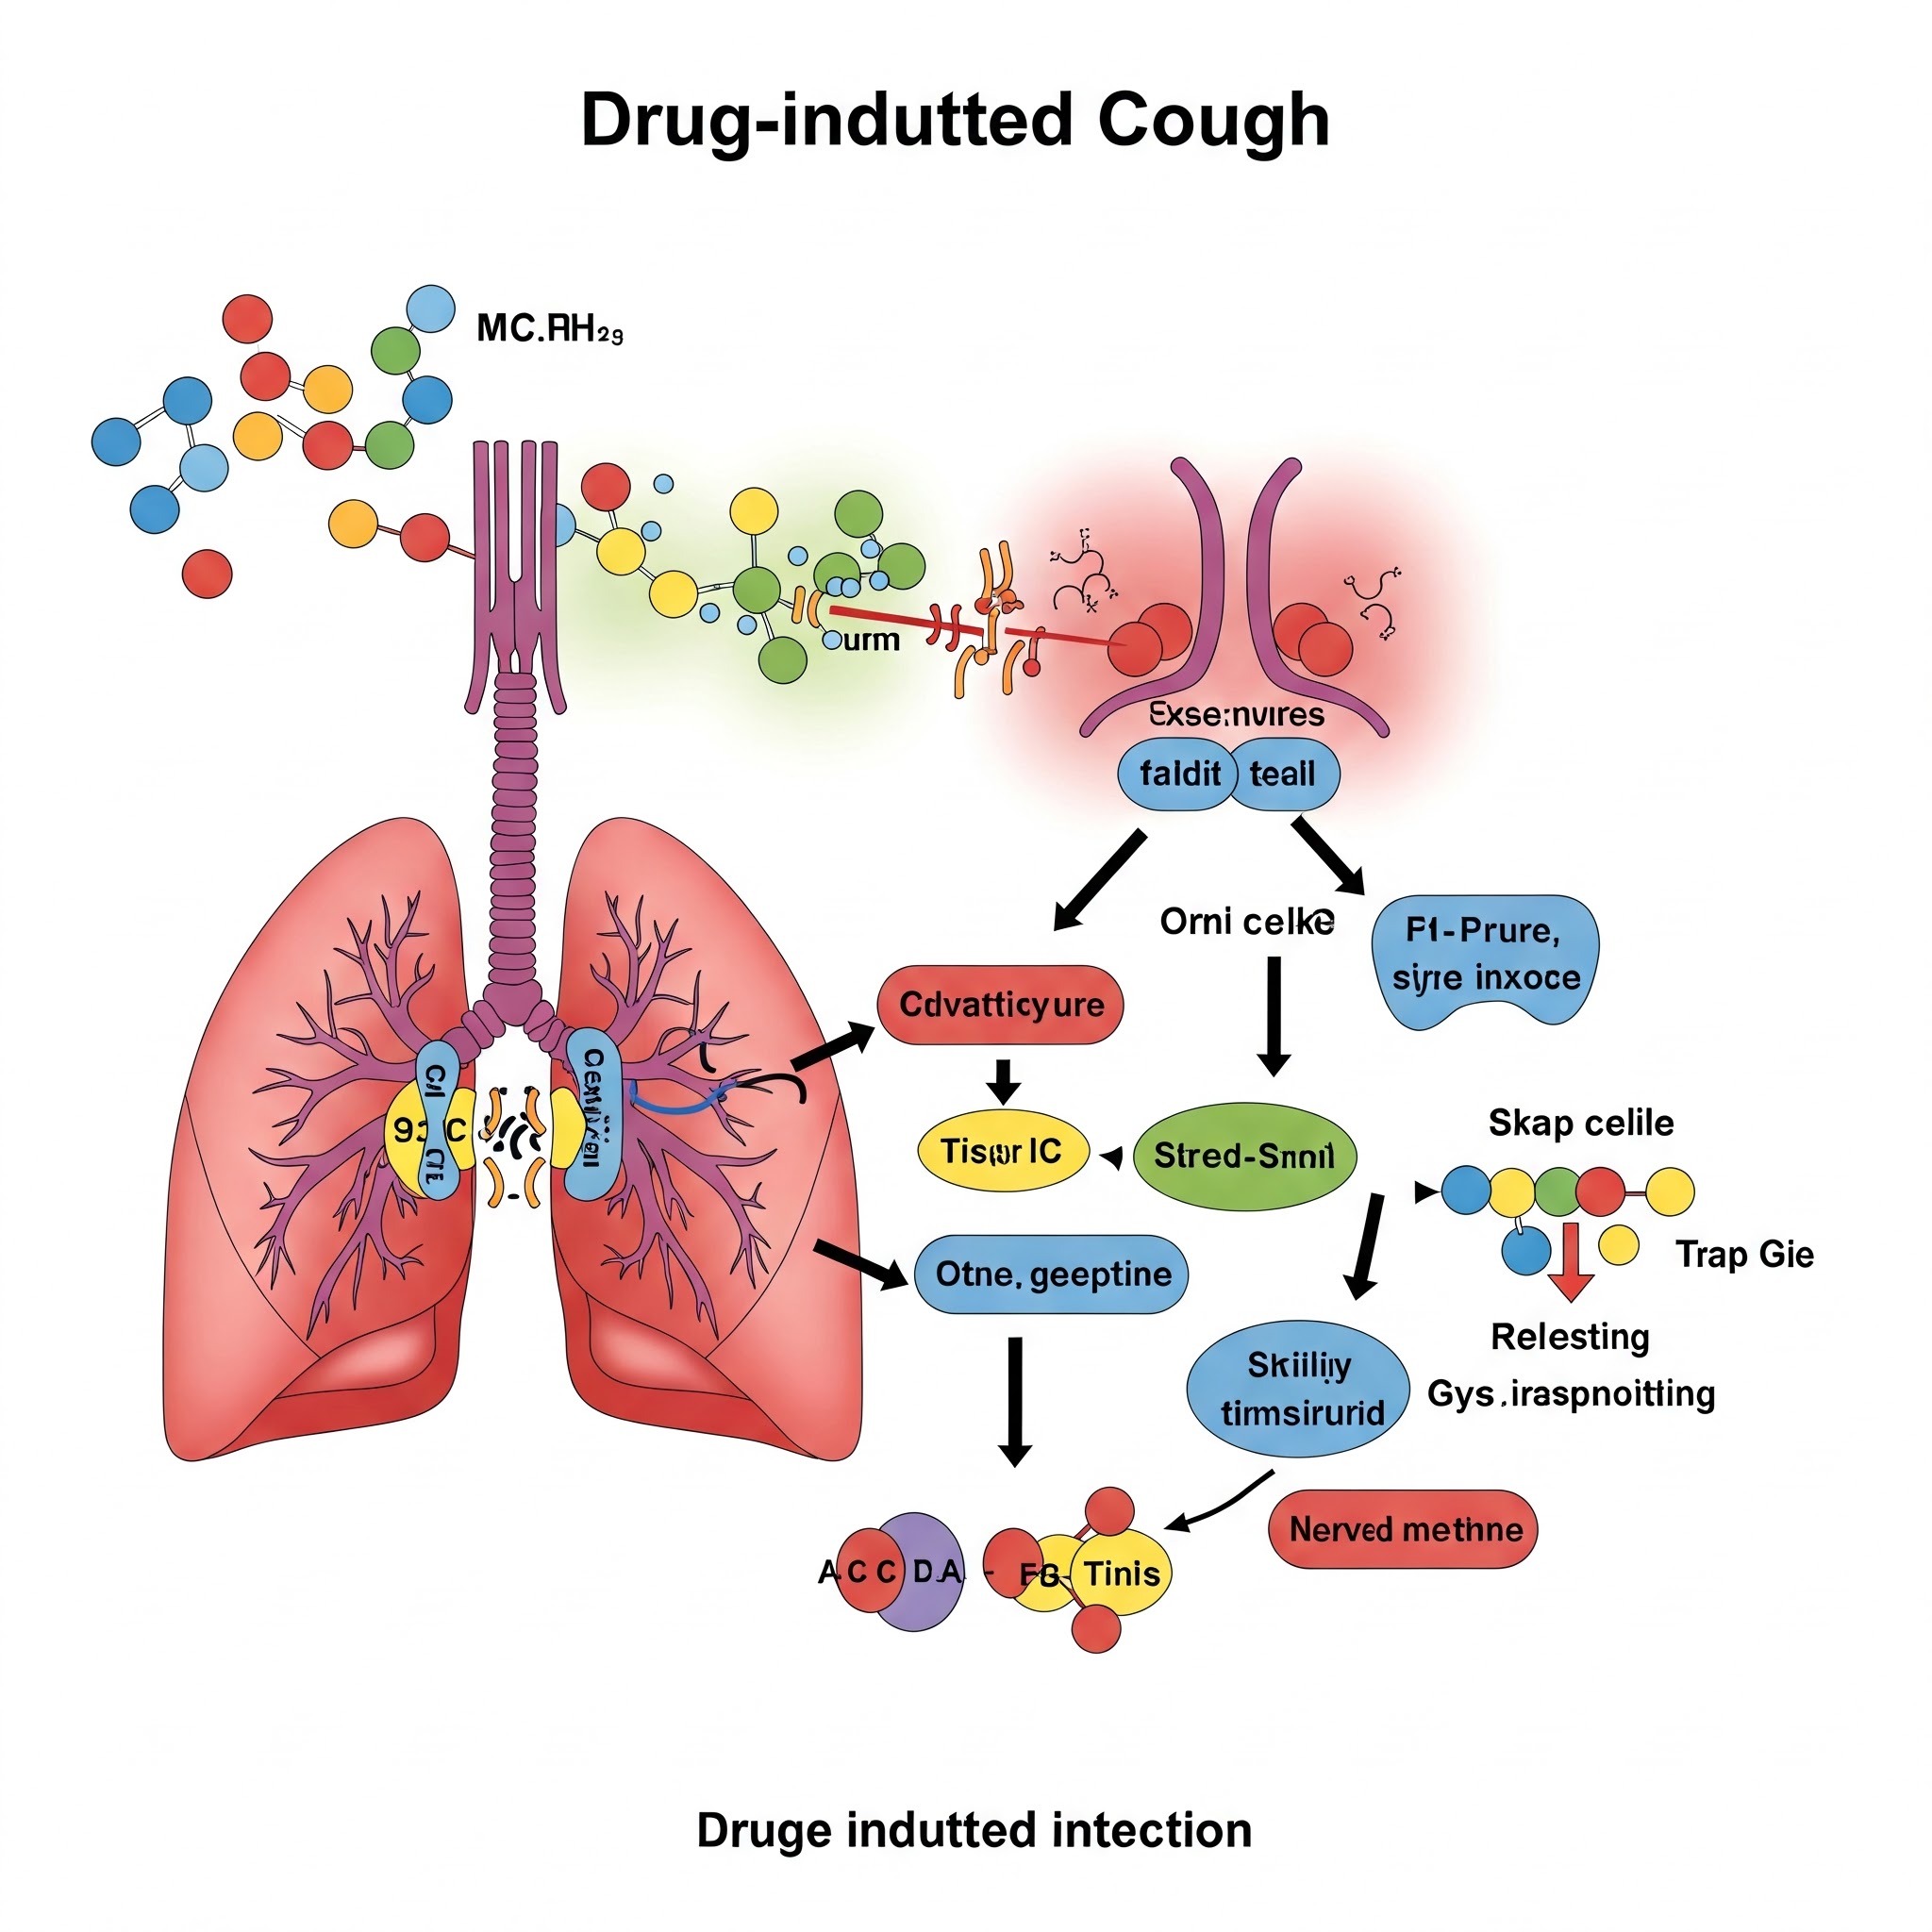

3.5. 약물 부작용: 놀랍게도 일부 약물, 특히 ACE 억제제 라는 혈압약은 마른기침을 유발하는 부작용이 있을 수 있습니다. 마치 예상치 못한 선물을 받은 것처럼, 약 복용 후에 기침이 시작되었다면 약물과의 관련성을 의심해 볼 수 있습니다. 이런 경우에는 약을 끊거나 다른 약으로 바꾸면 증상이 호전될 수 있습니다.

약물 부작용: 기침을 유발하는 원인 약물을 중단 하거나 다른 약으로 변경 하는 것을 고려해 볼 수 있습니다. 반드시 처방한 의사와 상담해야 합니다.